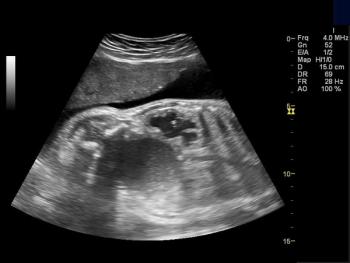

32-week pregnancy with anomaly.